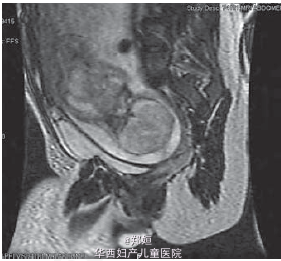

孕26周,大量羊水和早期宫缩出现 使用糖皮质激素 MRI提示,胎儿27周龄,颈部前方气道的地方有一9cm大小的肿块 抽取羊水1250ml并未减轻孕妇的不适和宫缩 孕28+4周破膜,行剖宫产,产下一男婴 术中尝试多种插管方式,硬性或软性的支气管镜检均失败 可见胎儿颈部有一巨大的肿块伸向胸部上方 手术切除该肿块,550g

病理学提示为未成熟畸胎瘤